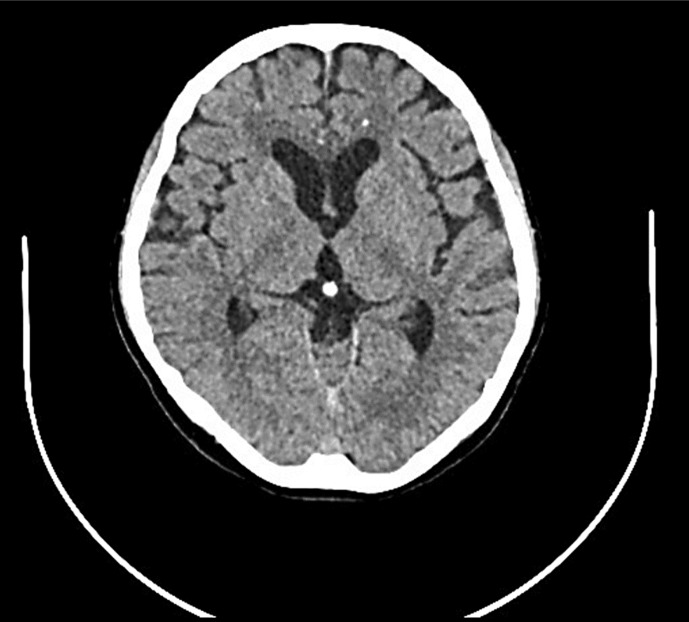

Case presentation: Cerebral magnetic resonance imaging showed confluent fluid-attenuated inversion recovery hyperintensities in the periventricular and frontal deep white matter, with multiple spotty calcifications in the frontal white matter by cerebral CT. Genetic testing revealed a mutation in the colony-stimulating factor 1 receptor (CSF1R).